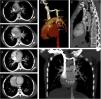

A 20-year-old female patient presented to our radiology department complaining of shortness of breath. Chest X-ray evaluation revealed tubular opacities in the lower zone of the left lung (Fig. 1A). Contrast-enhanced computed tomography (CT) showed non-enhanced tubular lesions compatible with mucocele in the superior and posterior segments of the left lower lobe (Fig. 1B). There was also air trapping in the lower lobe of the left lung (Fig. 1C and D). Three dimensional (3D) CT image demonstrated a persistent left superior vena cava in the left side of the mediastinum (Fig. 1E). The left superior vena cava was draining into the coronary sinus. It hadn’t any association with left pulmonary veins (Fig. 2A–G).

(A) Chest X-ray reveals tubular opacities in the lower zone of the left lung. (B) Contrast-enhanced CT shows non-enhanced tubular lesions compatible with mucocele in the superior and posterior segments of the left lower lobe. (C and D) There is also air trapping in the lower lobe of the left lung. (E) 3D CT image demonstrates a persistent left superior vena cava in the left side of the mediastinum.

Contrast-enhanced axial consecutive CT scans (A–D) reveal a left superior vena cava (dashed arrows) drained into the coronary sinus (arrow head). There is no association with the left pulmonary veins of the left superior vena cava. 3D volume rendered (E) and sagittal (F) and coronal (G) MIP CT images demonstrate clearly the left superior vena cava (dashed arrows) drained into the coronary sinus (arrow heads).